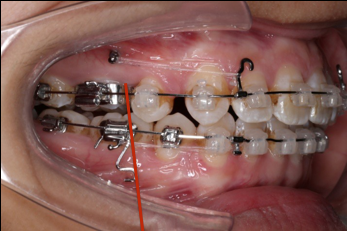

上颌矫治的生物力学

上颌使用高位种植钉及长牵引钩,配合尖牙近远中的v-bend,上颌前牙的牙齿移动方式是整体往上,往后内收。

下颌整平内收的生物力学

下前牙的压低+控制性倾斜移动内收,改善唇倾度,磨牙通过powerarm 直立,控根整体近中移动,使咬合高点的前移,整平下颌同时进行内收。